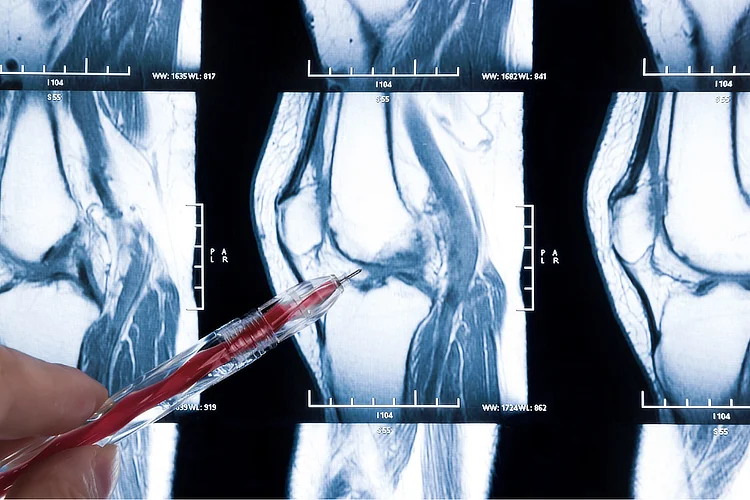

MRI scan of knee showing highlighted meniscus tear to assess cartilage damage.

• Magnetic Resonance Imaging (MRI) – Provides detailed images of knee structures to confirm the location and extent of the tear.